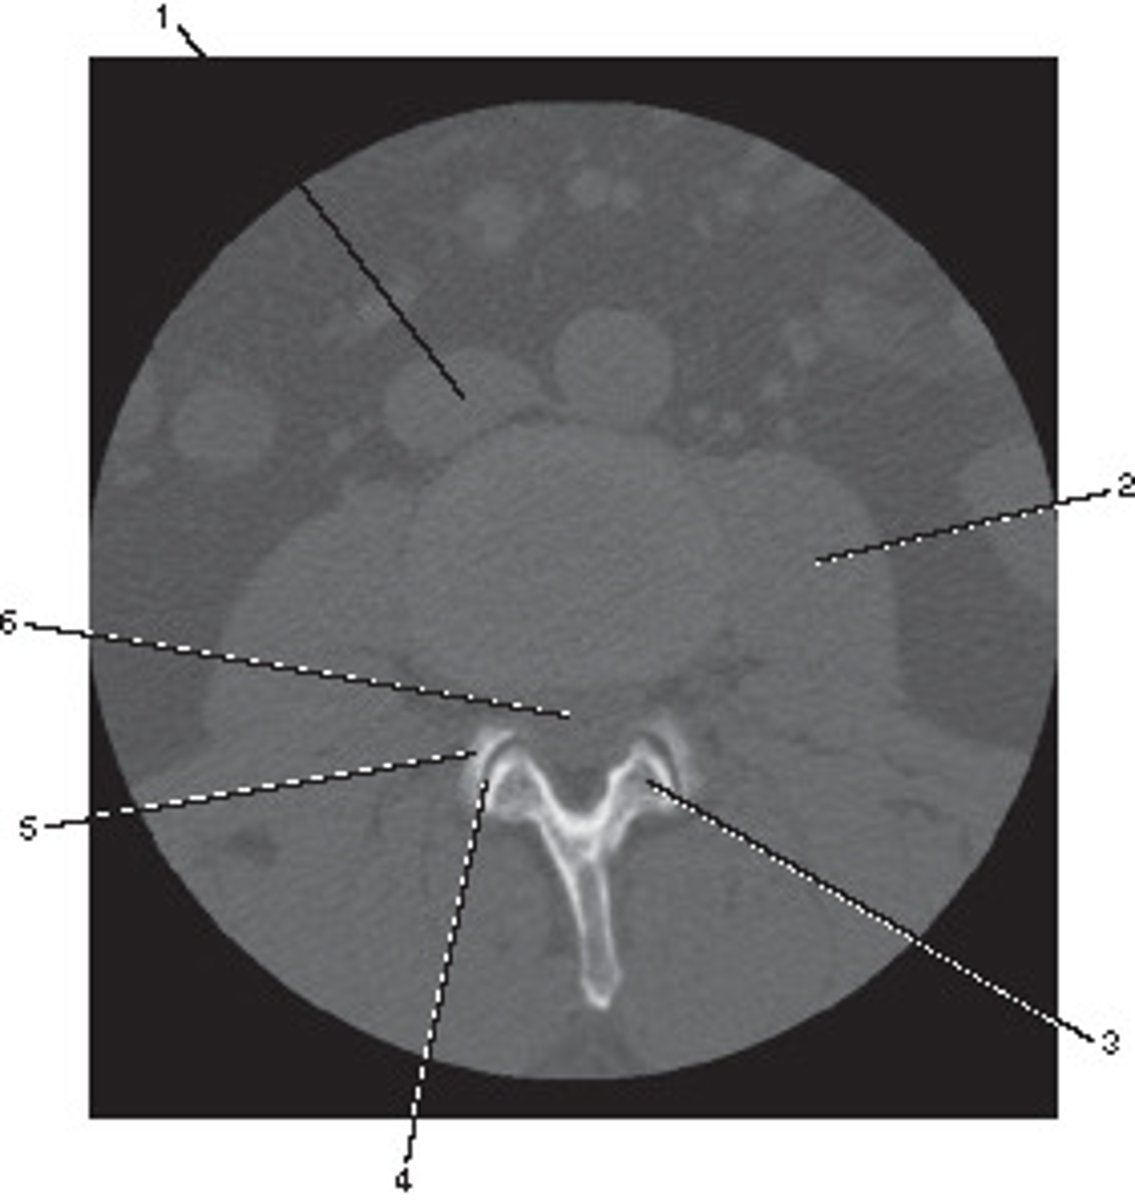

Body

Identify structure A on this axial CT slice of the lumbar vertebra.

<p>Identify structure A on this axial CT slice of the lumbar vertebra.</p>

Pedicle

Identify structure B on this axial CT slice of the lumbar vertebra.

<p>Identify structure B on this axial CT slice of the lumbar vertebra.</p>

Lamina

Identify structure C on this axial CT slice of the lumbar vertebra.

<p>Identify structure C on this axial CT slice of the lumbar vertebra.</p>

Transverse process

Identify structure D on this axial CT slice of the lumbar vertebra.

<p>Identify structure D on this axial CT slice of the lumbar vertebra.</p>

Posterior spinous process

Identify structure E on this axial CT slice of the lumbar vertebra.

<p>Identify structure E on this axial CT slice of the lumbar vertebra.</p>

Vertebral foramen

Identify structure F on this axial CT slice of the lumbar vertebra.

<p>Identify structure F on this axial CT slice of the lumbar vertebra.</p>